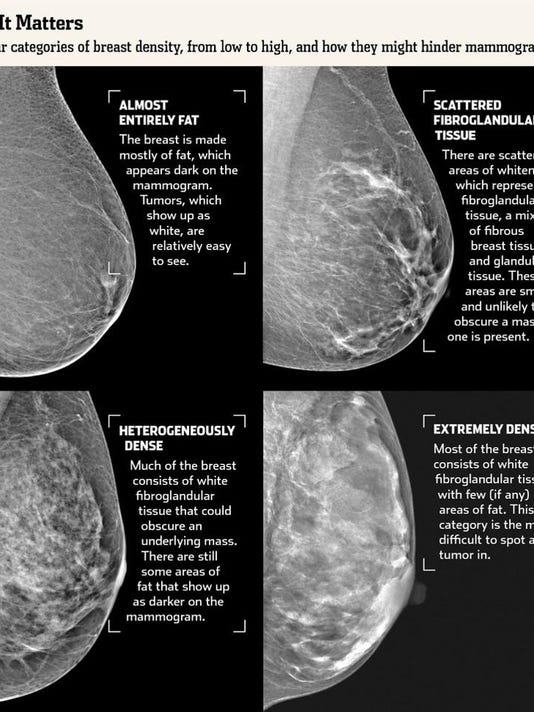

From www.huffingtonpost.com

Breast Density How to See Clearly Through the Fog HuffPost Glandular Density Breast  Breast density is a measure of how much fibrous and glandular tissue (also known as fibroglandular tissue) there is in your breast, as compared to fat tissue. Your breast is made of glandular, connective and fatty tissue. Breasts are made up of breast tissue (the milk ducts and lobules, which may be called glandular tissue) and fat. If a recent. Glandular Density Breast.

From blogs.womans.org

Breast Density Does it really matter? Life Among Women Glandular Density Breast  Dense breasts contain high amounts of glandular and fibrous tissue which appears white on a mammogram. Breast density is a measure of how much fibrous and glandular tissue (also known as fibroglandular tissue) there is in your breast, as compared to fat tissue. When you have dense breast tissue, that can make it harder to spot breast cancer on a. Glandular Density Breast.